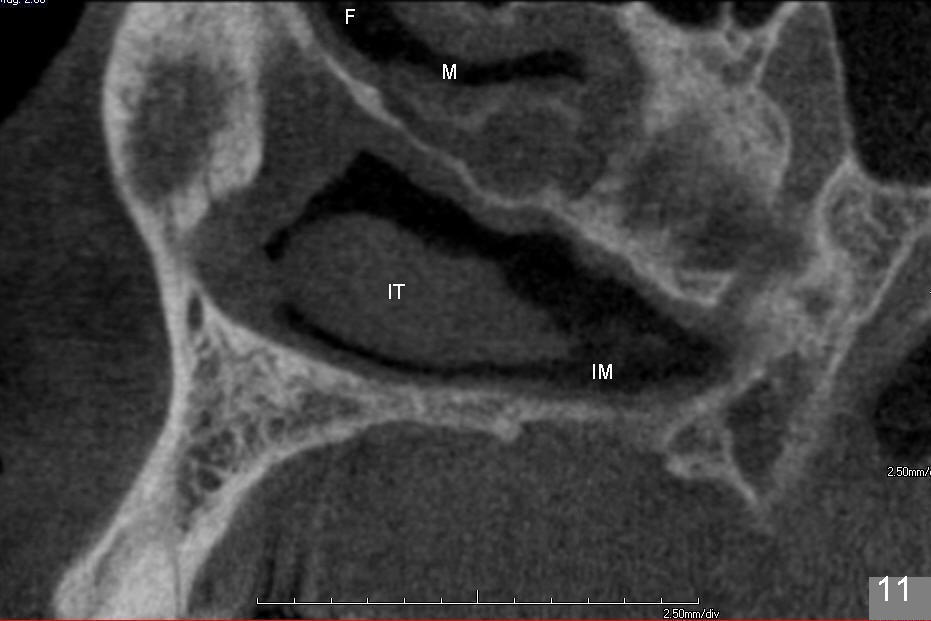

上颌窦手术后,病人即刻汇报患侧鼻塞,拍摄全景片,看不出来问题。给病人上颌窦术后医嘱,开喷鼻药(Afrin)和激素(Medrol Dosepak,减少水肿)。之后研究术前CT(图十至十二),但愿上颌窦分离内侧壁没有太过分。第二天鼻塞消失,病人并没有用喷鼻药,但是使用激素。